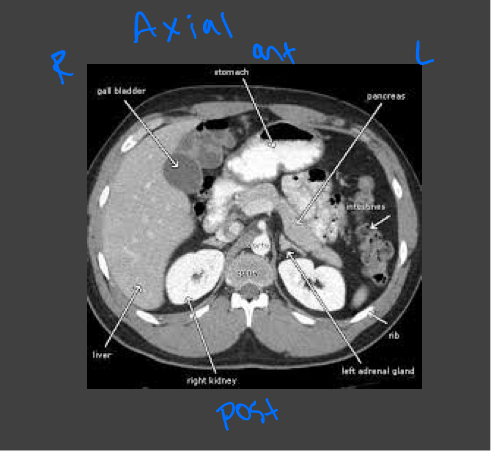

Axial CT images

Presented as if the viewer is standing at the foot of the patient’s bed; the patient’s right is to the viewer’s left; the anterior aspect of the patient is toward the top of the image